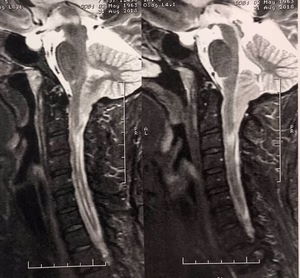

Sobre a Malformação de Chiari e seu tratamento.